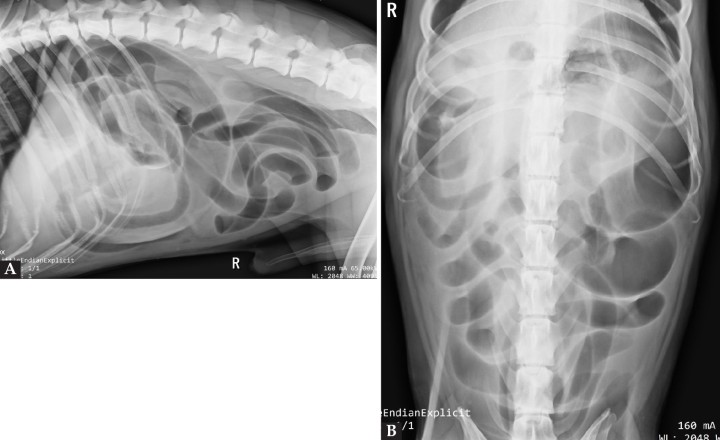

Se realiza un estudio radiológico de abdomen, en proyecciones lateral derecha y ventrodorsal (Fig. 1)

<p>Imagen radiográfica lateral derecha (<strong>A</strong>) y ventrodorsal (<strong>B</strong>) de la cavidad abdominal.</p>

Imagen radiográfica lateral derecha (A) y ventrodorsal (B) de la cavidad abdominal.